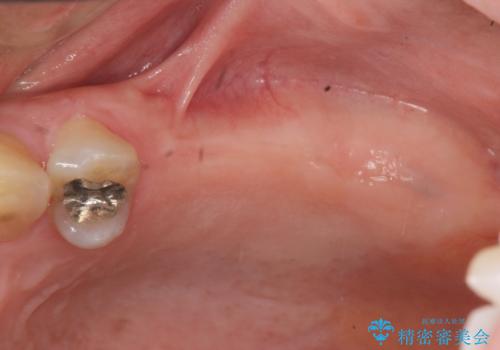

- 奥歯に入れていたブリッジがダメになり歯を抜去、全然噛めなくなった、インプラント治療を受けたい!と奥歯の機能回復を希望され来院されました。

奥歯はすでに3本失った状態で、この状態で歯を入れるには「入れ歯」か、「インプラント」の2択となります。

入れ歯ではなくしっかりと噛んで食事を楽しみたい。という強い希望から、インプラント治療を進めていくこととなりました。